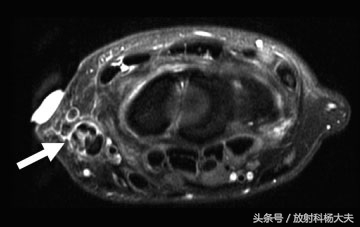

MR图象显示拇短伸肌腱部分撕裂,伴有周围积液,见下图。

参考文献及MR图片:

Musculotendinous Disorders in the Upper Extremity: Part 2. MRI of the Elbow, Forearm,

Wrist, and Hand, Russell C. Fritz, Semin Musculoskelet Radiol 2017;21:376–391.